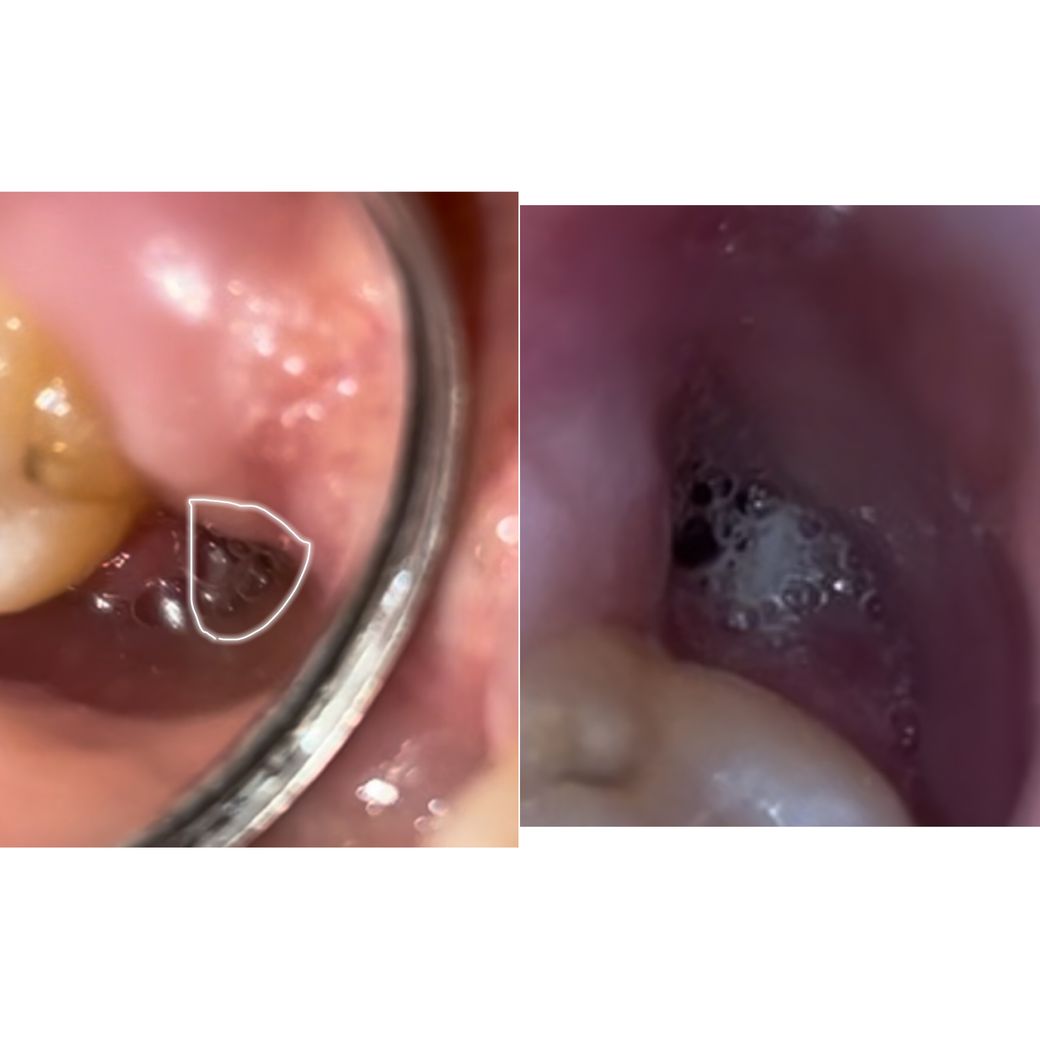

사진 자세히 찍는다고 찍었는데 침이 좀 고여있고 치아가 더러워서 혐오스러울수 있습니다!! ㅜㅜ

사진은 시간이 지나는 순서대로 올렸고 제일 마지막 사진엔 침이 좀 고여있는데.. 하얀색 저건 뭔지도 궁금하고요 ㅜ ㅜ

중간사진엔 볼록볼록 위아래 있던거같은데 아래에 있던 볼록이에서 마지막 사진 처럼 하얀게 튀어나온덜까요??

매복사랑니도 아니고 아랫니도 아니고 염증있던 치아도 아니라 뽑았을 때 안아팠는데 5일째까지 은은하면서 불편한 통증이 있으니까 걱정되네요 ㅠ ㅠ 드라이소켓 가능성이 있는건가요??

발치한 부위에 혈병이 제거되어 치조골이 구강내에 노출이 되면 감염이 되면서 드라이 소켓이 생길수 있습니다. 드라이 소켓이 생기면 악취와 통증이 있게 되요.

사진을 만 봤을 경우에는 드라이소켓의 여부를 파악하기는 힘드나 발치후에 통증은 대부분 1주일 이내로 줄어들게 됩니다.